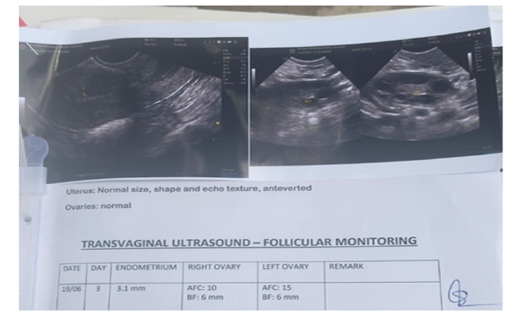

continue normal sexual activity for next 3 months. A Transvaginal

ultrasound on 19 June 2025 for monitoring follicular phases,

showed endometrial thickness of 3.1mm, Right ovary-AFC10, BF:

6mm and Left Ovary AFC-15mm and BF:6mm. Surprisingly the

lady had her LMP on 18 June 2025. An Obstetric for first trimester